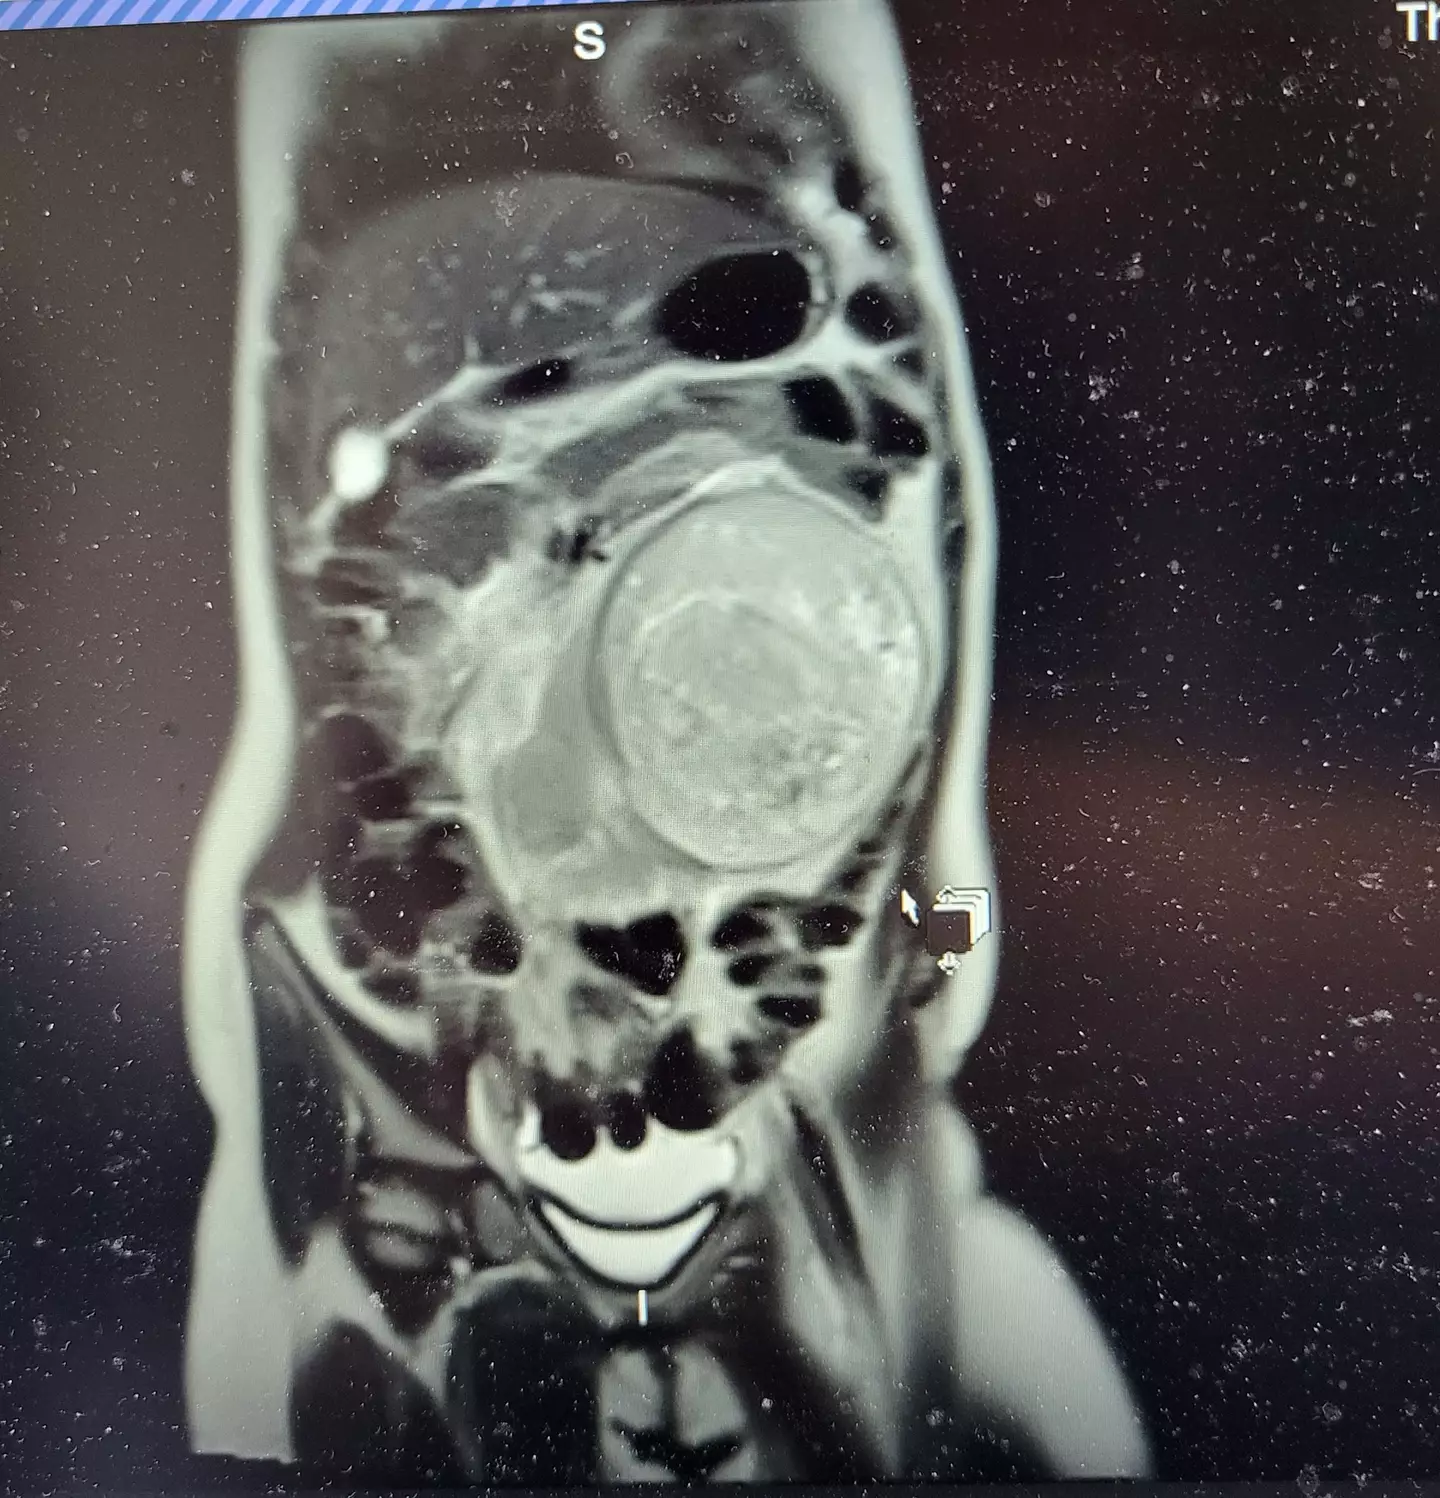

But when Mia turned 'grey', a visit to A&E revealed that her red and white blood cells weren't normal and an ultrasound showed that the schoolgirl had an 11cm (4.3in) tumour in her left kidney.

Mia was diagnosed with stage two kidney cancer and a Wilms' tumour on New Year's Eve last year.

After being told of the rare kidney tumour, it was confirmed that 'it was a stage two Wilms' tumour', said Molly.

An operation took place in February to remove the tumour and kidney which was ultimately successful, though Molly described the experience of seeing her daughter in intensive care as 'horrendous'.